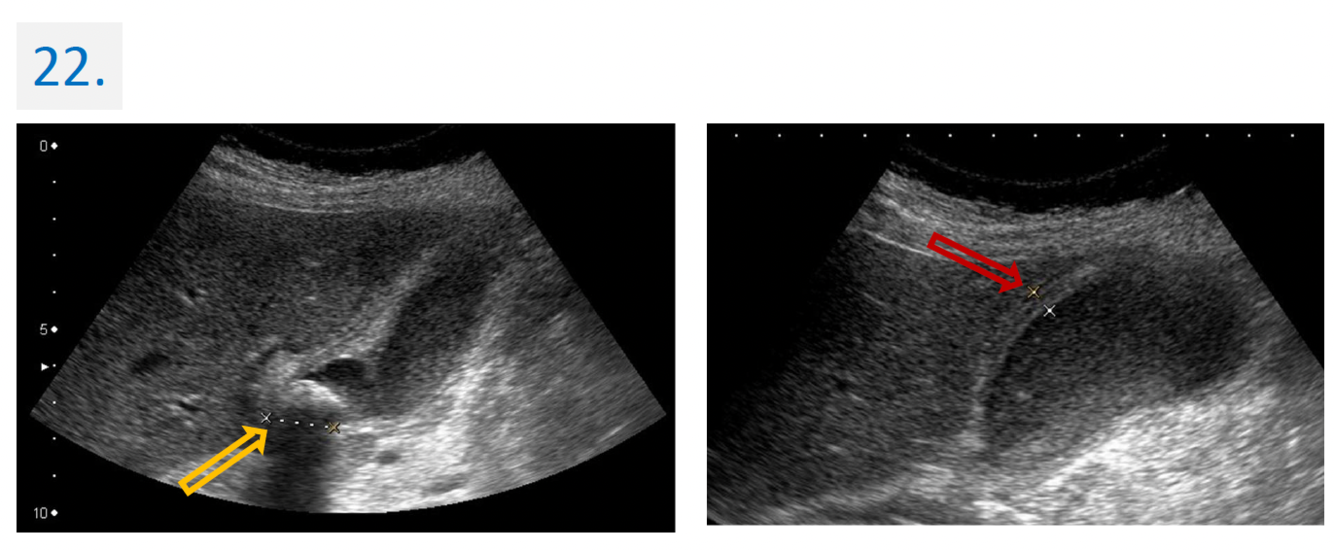

22

Diagnosis:

Acute cholecystitis with gallstone